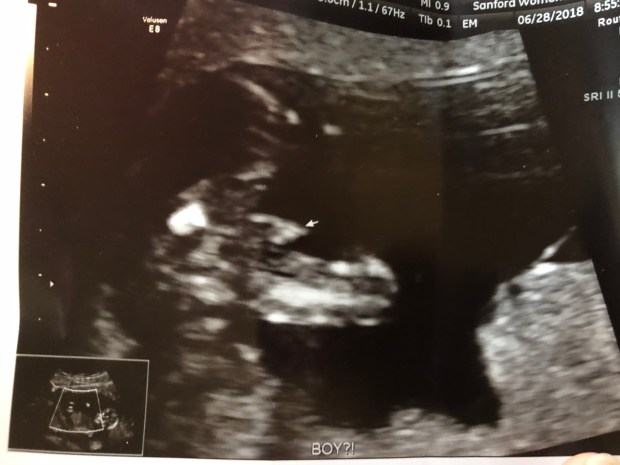

I shared on my Facebook page about a week ago, that we are 95% certain on the gender of our little one!!!!  I didn’t anticipate learning of this news until our 20 week ultrasound, but was pleasantly surprised when our latest ultrasound revealed a very telling couple of scans!!!

The tech went through all of the many angles and measurements and scans that were needed for the screening.  She was quick to assure us that everything looked great as far as she could see!  She then asked us if we were going to find out the gender when that time came.  I assumed she was making small talk and answered quickly that yes, we would find out as soon as we could.  This was followed by silence and I began to wonder, could she possibly tell??  I was only 13 weeks 3 days along, baby couldn’t possibly be big enough to reveal their gender to us, could they?  So I anxiously asked!

She continued to scroll the wand over my abdomen and said she would try for us at the end of the scan.  As long as baby would cooperate, she may be able to tell.  She said the boy parts are discoverable depending on the “angle of the dangle” and girl parts are typically very swollen at this stage due to all the hormones, and makes it able to determine the gender….as long as baby cooperates ๐Ÿ˜‰  She did warn us that it could be inaccurate and that we probably were best off not going out and buying too many gender specific items…just incase.

When the time finally came that the tech could pay special attention for those special parts, baby didn’t want to move anymore {of course}!  She angled the wand differently and gently poked on my belly to see if she could get them to move.  After a couple of minutes of this, she informed us disappointedly we may not yet get to learn what baby is.  And then, baby moved!  We could easily make out the spread legs and she pointed out the area revealing our baby’s gender.  She was 80% sure on what what she was seeing, which felt pretty confident to us!  Then, baby moved a little more, making it much clearer and easier to see what we thought we were seeing!!!  Her estimate bumped up to 95% confidence on the gender!